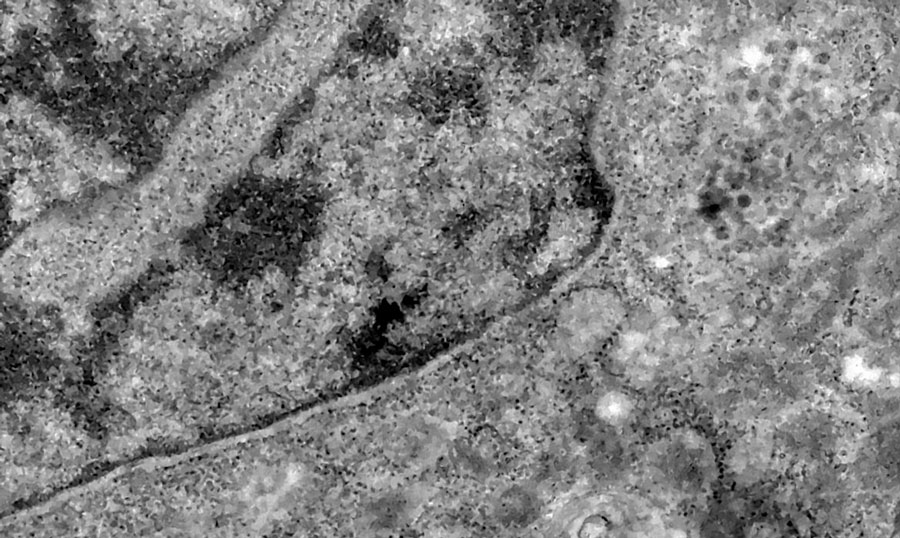

Nos casos analisados, constatou-se que a variante é portadora de dezenas de mutações genéticas que podem afetar os índices de contágio e de letalidade. A OMS, entretanto, afirmou que ainda não há estudos suficientes para afirmar as propriedades da Ômicron, mas que já existem esforços científicos acelerados para estudar as amostras. Um time de cientistas de universidades da África do Sul está decodificando o genoma da Ômicron, juntamente com dezenas de outras variantes do novo coronavírus.

Tulio de Oliveira, diretor do Centro para Respostas e Inovações Epidêmicas da universidade de KwaZulu-Natal, afirmou em coletiva de imprensa que a variante Ômicron possui “uma constelação incomum de mutações”. A variante Delta, por exemplo, possuía duas mutações em relação à cepa original do novo coronavírus, enquanto a Ômicron possui cerca de 50 – 30 delas localizadas na proteína Spike, responsável por infectar células saudáveis, explicou o brasileiro.